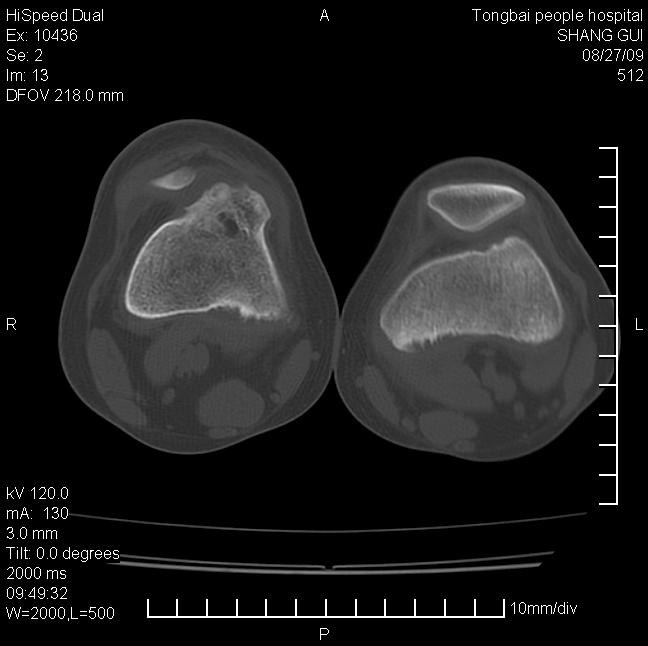

女,12岁。无意发现股骨下端隆起。局部皮肤颜色,温度无异常。

考虑右股骨下端骨纤维结构不良;不排除非骨化性纤维瘤。

不能排除,其实平片更直观。宽基底骨软骨瘤皮质与骨干皮质相连,髓腔与髓腔相通,骨纹理走行方向一致,部分软骨帽可有钙化,本例病变内“磨玻璃状、多囊状改变”比较符合骨纤。